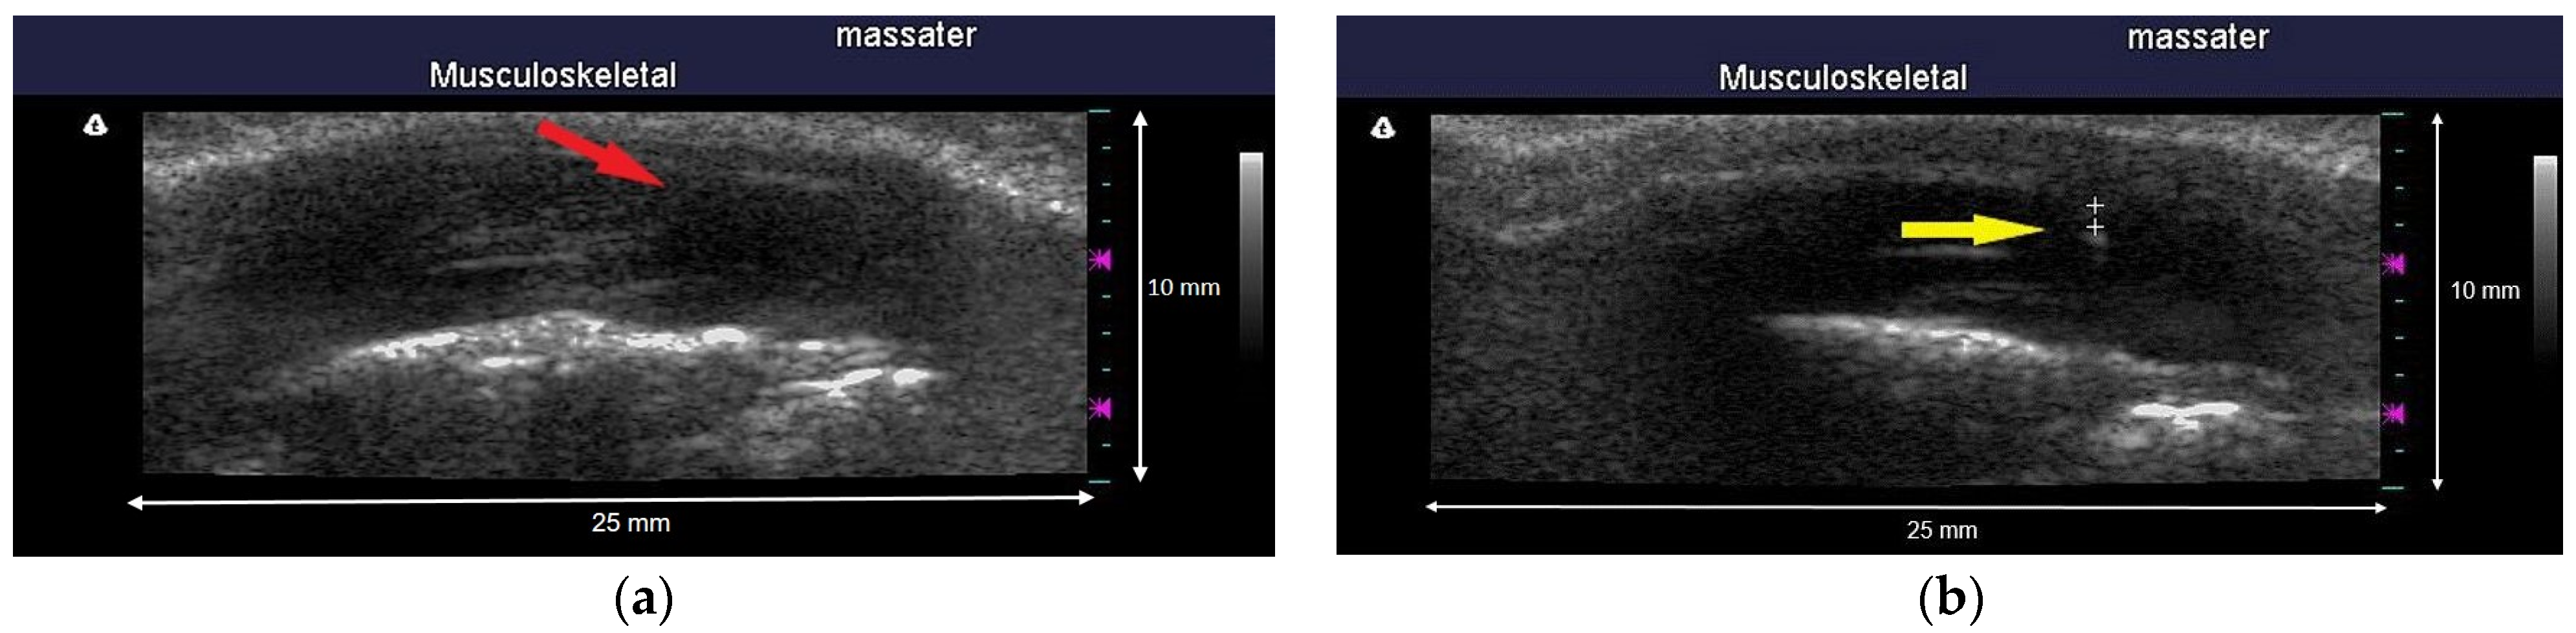

2.4. Ultrasound Imaging

4.1. Hypoechoic Characteristics of MTrPs